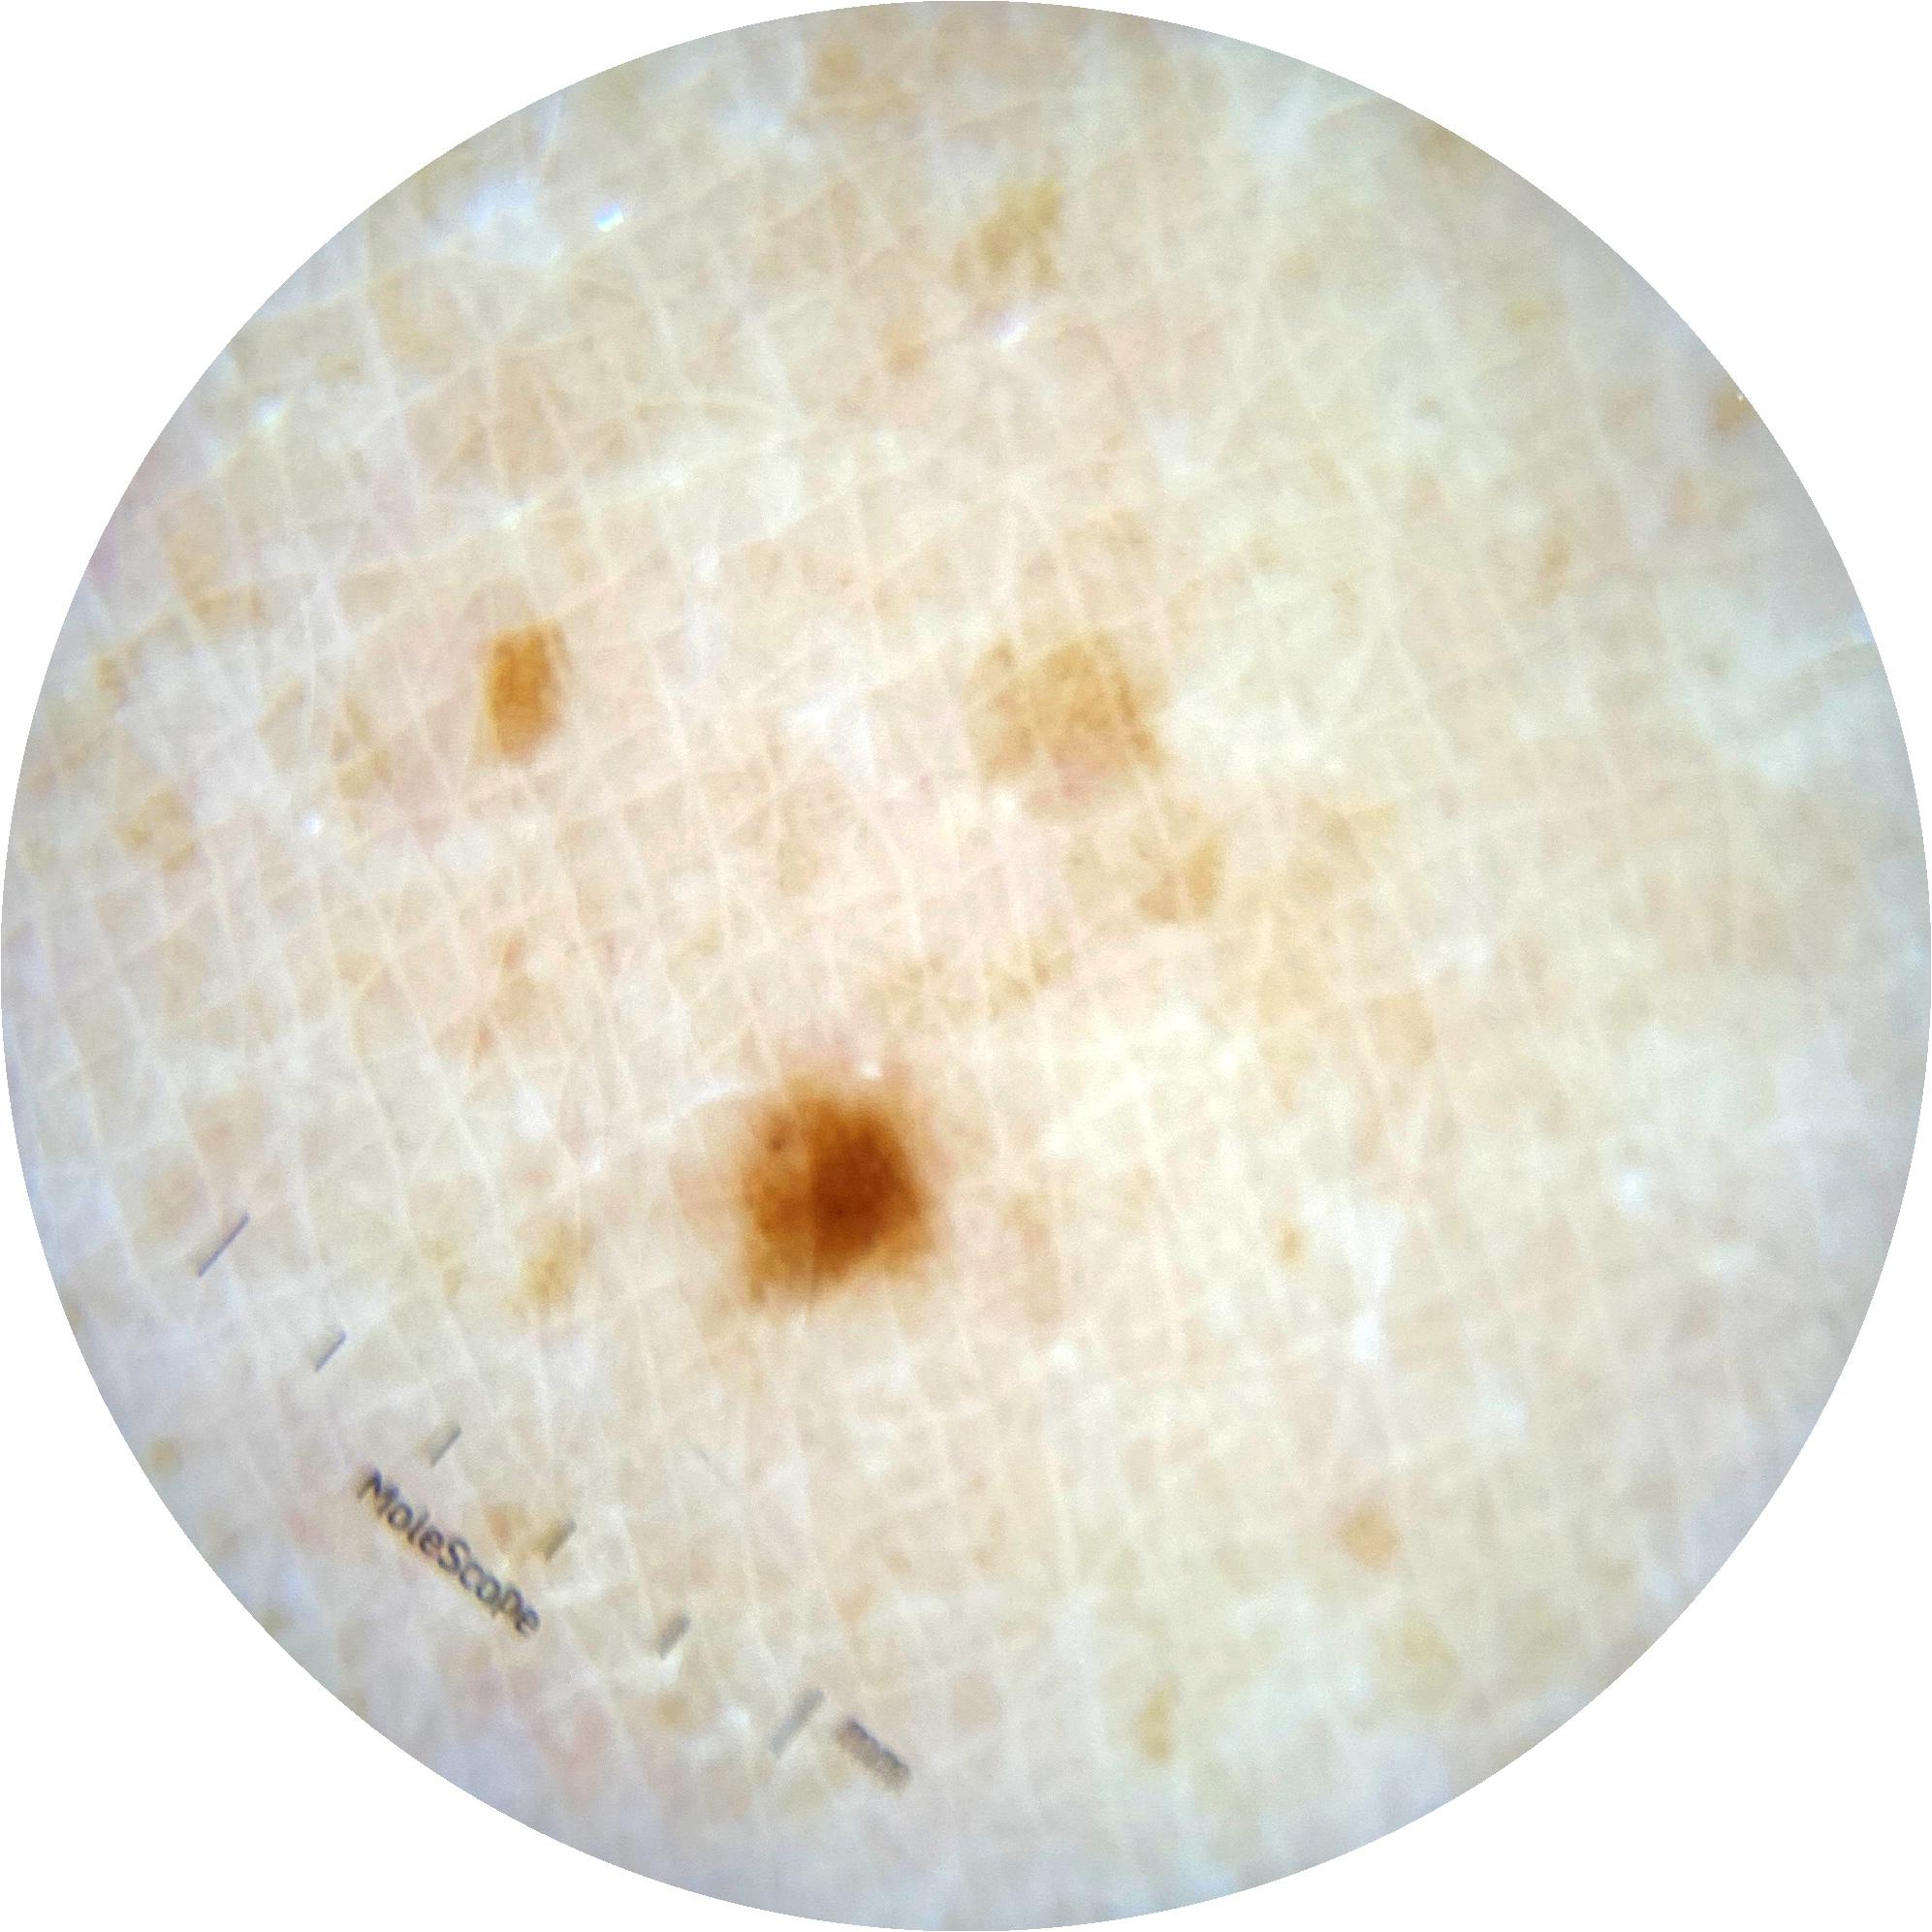

ISIC_5667482

1987 x 1987

Clinical

Field Value

acquisition_day 272

age_approx 45

anatom_site_1 Trunk

anatom_site_2 Posterior trunk

anatom_site_general posterior torso

diagnosis_1 Benign

image_type dermoscopic

lesion_id IL_5659437

patient_id IP_3828705

personal_hx_mm True

sex male